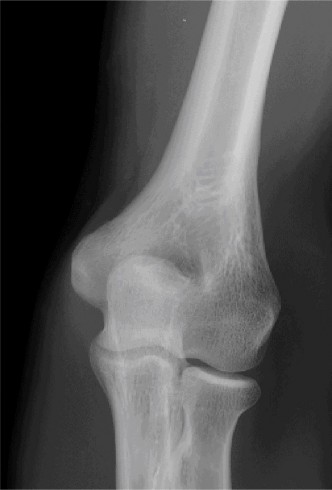

Treat a patient with infected total shoulder arthroplasty? CASE 21 A 70-year-old, right-hand-dominant female presents to clinic complaining of 4 years of gradually worsening chronic right shoulder pain and stiffness. She says the pain is worse at night and with any range of motion, denies a history of trauma, pain in other extremities, or numbness or tingling of the right upper extremity. She notes that her mother suffered from rheumatoid arthritis that affected her shoulder. Physical examination reveals decreased muscle bulk over the right supra- and infraspinatus fossae compared to the contralateral side, limited active and passive ROM, marked weakness with external rotation, and 4+/5 strength with shoulder abduction. X-rays of the right shoulder are shown in Figures 2–58 and 2–59.

Figure 2–58

Figure 2–59

The correct answer is (C). Rotator cuff tear arthropathy consists of a combination of rotator cuff insufficiency, glenohumeral joint degenerative changes, and superior humeral head migration. It is more common in women and also more often found on the dominant side. The patient’s clinical examination with weakened external

rotation and muscle atrophy signaling incompetent supra- and infraspinatus muscles point to rotator cuff insufficiency, and her plain films reveal narrowed glenohumeral joint space as well as superior migration of the humeral head. Choice D is incorrect because, while radiographs would show narrowing of the glenohumeral joint space, they would also likely show numerous osteophytes and posterior wear of the glenoid. Choice B is incorrect because, while adhesive capsulitis does present as decreased active and passive range of motion, the patient’s constellation of symptoms pointing towards rotator cuff insufficiency along with the radiographs make cuff tear arthropathy the more likely choice. Finally, Choice A is incorrect because even though she has a positive family history of rheumatoid arthritis, it is less likely to present only in a single joint. Also, rheumatoid arthritis on radiography appears more as an erosive process without the characteristic superior migration of the humeral head.

The correct answer is (A). Superior migration of the humeral head would be most indicative of chronic rotator cuff insufficiency associated with cuff tear arthropathy, as it is a direct result of the inability of the rotator cuff tendons to help maintain the humerus in its normal position. Acetabularization of the undersurface of the acromion is commonly associated with superior migration of the humeral head found in rotator cuff tear arthropathy, and can be assessed using the Hamada classification, which is based on measurements of the acromiohumeral interval on radiography (Table 2–8). Choices B and C are incorrect because, while narrowed glenohumeral joint space and subchondral sclerosis are associated with rotator cuff arthropathy on radiographs, they indicate degenerative joint changes rather than chronic rotator cuff insufficiency. Choice D is incorrect because it is not a specific sign of rotator cuff arthropathy.